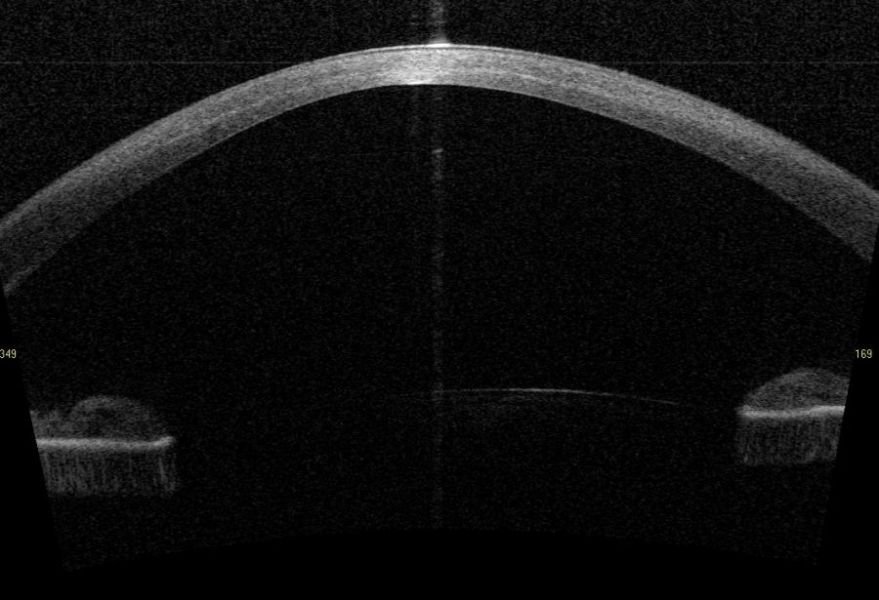

optische Kohärenztomographie der Vorderabschnitte (Abbreviations & acronyms: VA-OCT)

optische Kohärenztomographie des Vorderabschnitts (Abbreviations & acronyms: Vorderabschnitts-OCT, VA-OCT)Translations

English | anterior segment optical coherence tomography |